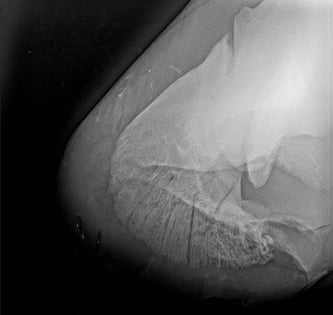

Die Untersuchung in der Pferdeklinik Neugraben in Niederlenz hat die Diagnose Fissur Hufbein ergeben.

Nach zwei Wochen Boxenruhe verschlechterte sich der Zustand des Hufbeins akut. Der Wallach wurde erneut in der Pferdeklinik Neugraben untersucht und schliesslich den Bruch des Hufbeins festgestellt.